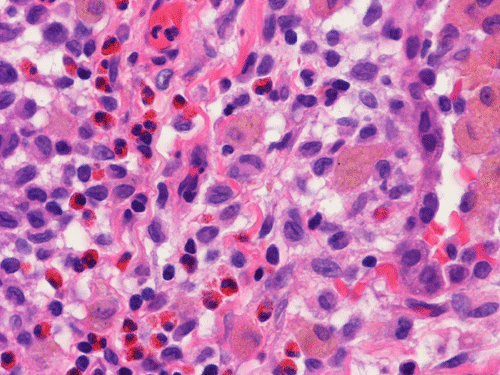

At scanning magnification (Panel A), the lung parenchyma is replaced by some coalescing fibrous nodules. The degree of involvement is variable at different fragments (Panel B and C). In the less affected areas, there are some fibrotic thickening of the septa (Panel C). In some areas, the changes are minimal and the pleural appear to be uninvolved (Panel D and E). In low to medium magnifications, these nodules of fibrosis contains a large number of hemosiderin laden macrophages (Panel F and G) admixed with fibrous tissue. The diagnostic tissue, however, is present in areas with increased cellularity. In these areas, there is a background of cells with a moderate amount of cytoplasm and bland nuclei. Some of these nuclei have kidney shape (arrow in Panel H). In some areas, many of the nuclei have a deep nuclear groove that resemble a coffee bean (arrow in Panel I). In the third type of areas, the nuclear grooving is not distinct (Panel J). Prominent eosinophilic infiltrations are almost always present. Immunohistochemistry on CD1a revealed many positive cells (Panel L). Also present in the specimen are multiple small blood vessels with thickened intima (Panel K). A Movat pentachrome stain demonstrates an internal elastic layer in these vessels and confirms that these are arteries (Panel M and N).

Pathologically, PLCH can be broadly divided into an early or cellular stage and a late or fibrotic stage. Demonstration of LCs is of critical importance for a correct diagnosis. The morphology of LCs is similar to LCH in other organs. LCs are characterized by a deep nuclear groove which lead to “coffee bean-shaped” or “kidney-shaped” nuclei. In most cases, the level of atypia and pleomorphism is low. A moderate amount of amphophilic to weakly eosinophilic cytoplasm is present. The cytoplasmic membrane is indistinct. Eosinophils and chronic inflammatory cells, varying from scant to abundant, are present. Except for a scant frankly pleomorphic cases, the level of pleomorphism and atypia is minimal to low. Eosinophilic abscesses with central necrosis may be present. Immunohistochemically, LCs are similar to their normal counter parts and are positive for CD1a and S100. At the ultrastructural level, Birbeck granules can be demonstrated. For most cases, the diagnosis can be established by histopathologic criteria but these additional features help to confirm the diagnosis.

Histopathologic signature of Langerhans cell histiocytosis, namely kidney shaped or coffee bean shaped, bland nuclei associated with eosinophilic infiltration is not difficult to see in most of the cases. The amount of eosinophilic infiltration and the proportion of cells with nuclear grooving, however, can be quite variable but this problem can usually be overcome by a diligent search. Demonstration of CD1a by immuhonistochemistry or Birbeck granules by electron microscopy will confirm the diagnosis.